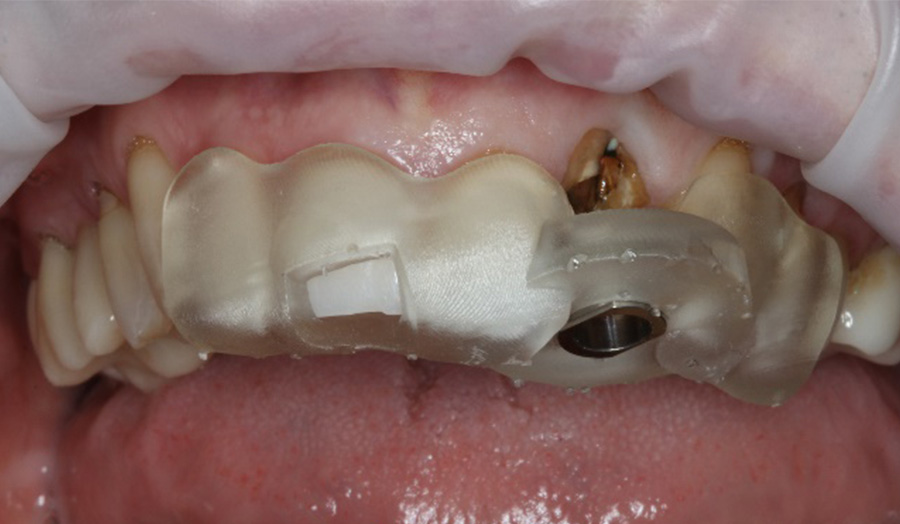

A 62-year-old male presented himself to my practice with a fractured non-restorable tooth #10. We planned a single implant with a surgical guide and a temporary bridge, both manufactured with Primeprint. The surgery was completed in 20 minutes, and it took us 10 minutes to bond the temporary bridge.

Usage: Placing the 3D-printed surgical guide with Primeprint Guide material with excellent fit

After: Placing the 3D-printed One-wing-Maryland Bridge with Primeprint Temp material as a temporary restoration